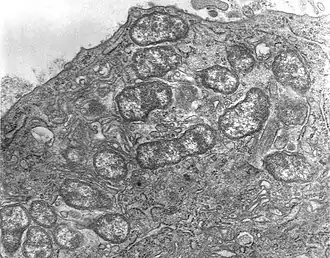

Description de l'image Orientia tsutsugamushi.JPG.

Orientia tsutsugamushi, unique représentant du genre Orientia, est une espèce de bactéries responsables de la fièvre fluviale du Japon.